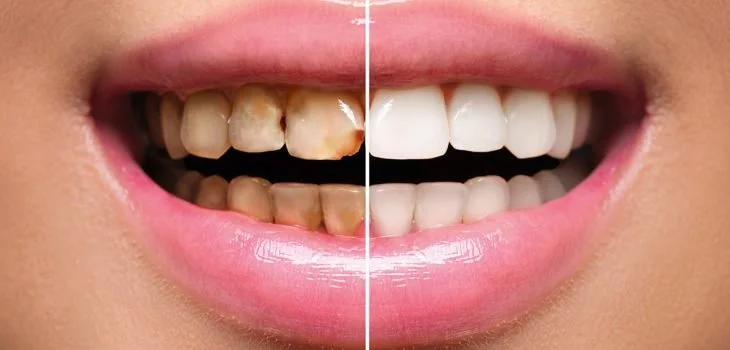

Restorative Dentistry

Restore the function and beauty of your smile with our restorative dentistry solutions. Whether you need fillings, crowns, bridges, dentures, or snap in teeth rest assure we are equipped with state-of-the-art technology and expertise to address a variety of dental issues. Our goal is to provide durable, natural-looking restorations that seamlessly blend with your existing teeth, ensuring both strength and aesthetic appeal. Trust us to restore your smile to its full potential with precision and care.

Fillings

Fillings and sealants are common dental treatments used to protect and restore teeth. Fillings are used to repair cavities or damaged teeth by filling the affected area with a durable material, such as composite resin or amalgam, to restore the tooth's structure and function. Sealants, on the other hand, are a preventive measure, involving the application of a thin, protective coating to the chewing surfaces of the back teeth, creating a barrier that helps prevent cavities by keeping out food particles and bacteria.